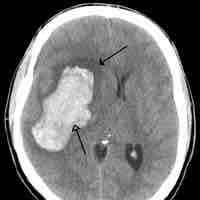

Traumatic Brain Injury

Traumatic brain injury (TBI) occurs when an external force injures the brain and can be caused by a direct impact or by acceleration alone.

Thumbnail

Cerebrovascular Accident

A cerebrovascular accident results from loss of oxygenated blood to a region of the brain and is typically accompanied by neuronal loss.

Brain Tumors

A brain tumor is a pathological abnormal growth of cells in the brain.